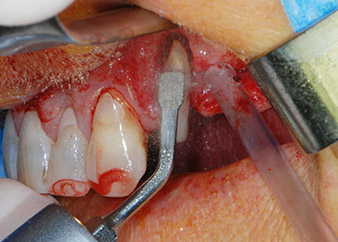

One month later, on the day of surgery, pain and inflammation at tooth 24 were minimal, but mobility of Miller class 2 was still present. After opening the flaps and cleaning the periapical and peri radicular infected tissue, the extent of the bone defect became obvious (Figs. 2 and 3).

At the buccal root, all vestibular and distal bone was missing. Attachment was essentially restricted to the palatal root, underlining the preliminary poor prognosis. Tooth 27 also showed a reduced horizontal attachment and a minimal apical rarefaction (cf. Fig. 1) without clinical symptoms.